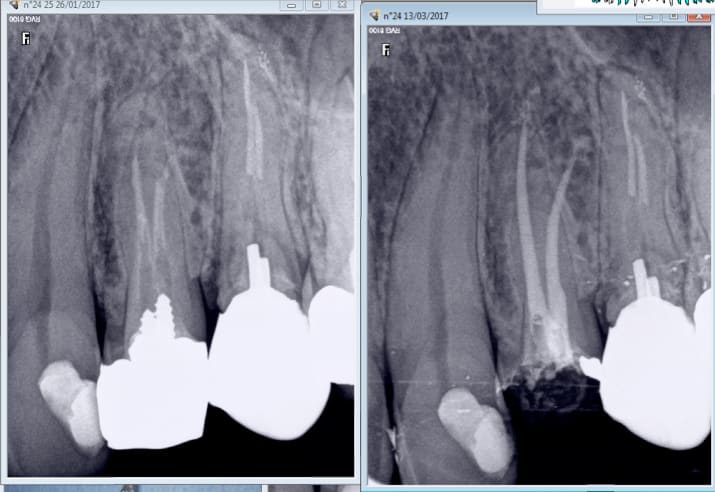

Casa je viens encore de reprendre un de tes traitements. Appliques toi merde ! -)))

Capture d écran 2017 03 13 10.28 - Eugenol

Capture d écran 2017 03 13 10.31 - Eugenol

Ici les 2 vont avoir droit à leur ic coiffe ( CMU) et pourtant un ic tarif CMU ca ne rapporte pas bésef.